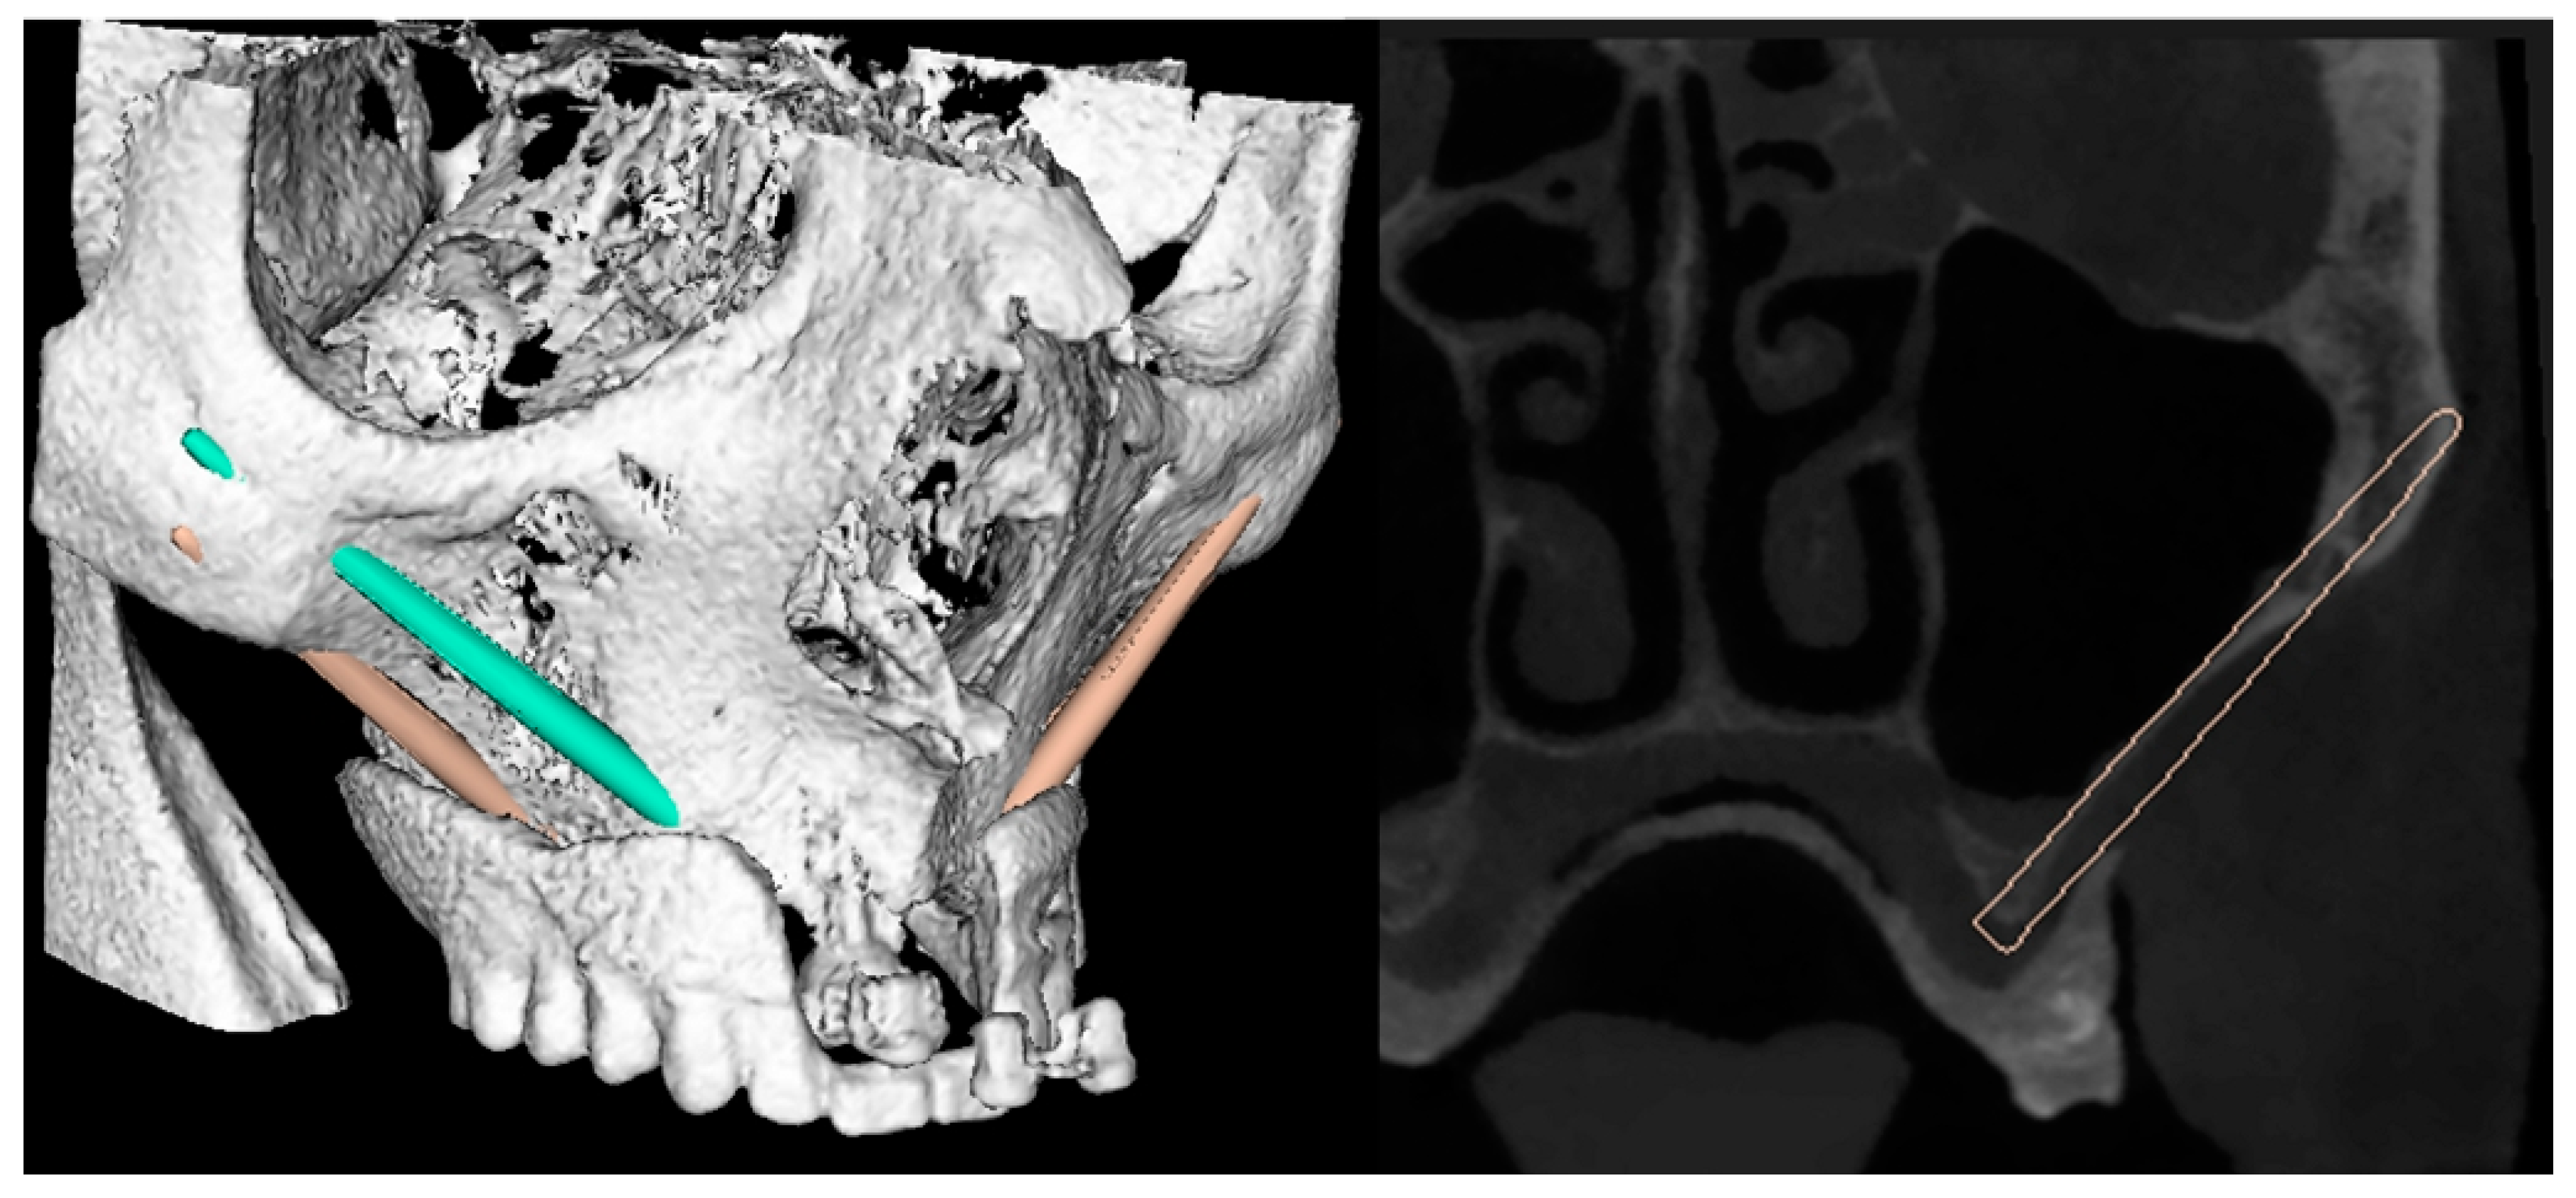

2. Case Report

- Step 1. Scanning of the patient and the scan prosthesis/registration template, external registration frame, or bone markers.

- Step 2. Software planning of the implant position.